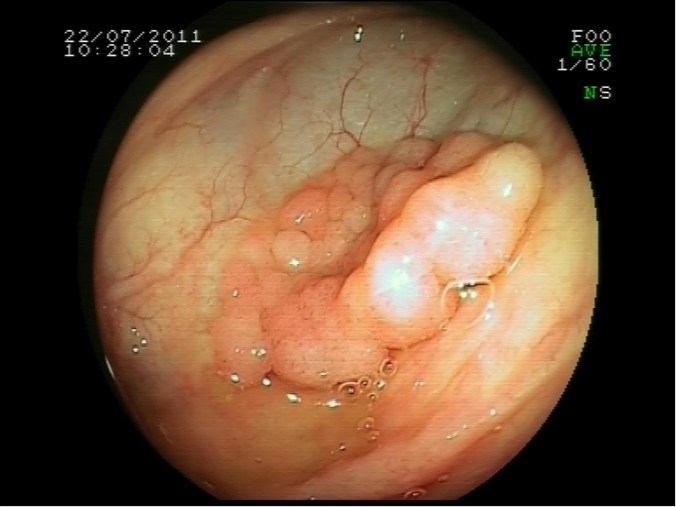

Polipectomía en ciego